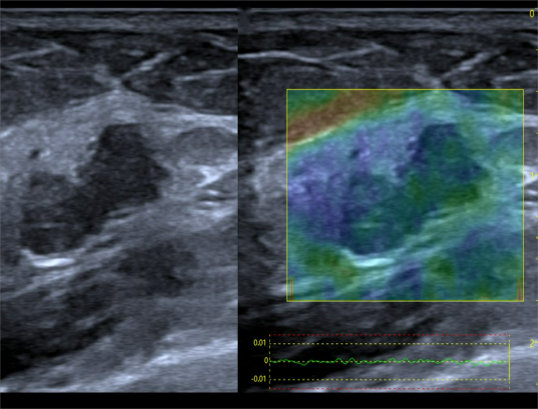

Freehand elasticity imaging: 徒手弹性成像(FEI)

• 徒手弹性成像是通过移动探头对检测部位进行挤压使组织产生运动,并利用回波信号进行运动检测得到表征组织弹性的应变图像

• 基于应力的弹性应变成像,提供组织软、硬病变的诊断信息

• 业界最高帧率 50fps vs 20fps

• 业界最大检测区域—全器官检测